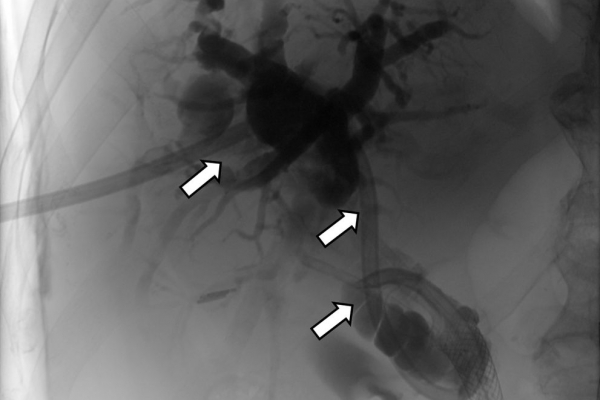

Σε πολλές περιπτώσεις πρωτοπαθών ή δευτεροπαθών όγκων ήπατος - παγκρέατος προκαλείται απόφραξη των χολαγγείων με συνοδό αποφρακτικό ίκτερο.Ο ασθενής με αποφρακτικό ίκτερο δεν μπορεί να υποβληθεί σε χημειοθεραπεία, αν δεν αποκατασταθεί ο ίκτερος με παροχέτευση των χοληφόρων.

Η παροχέτευση των χοληφόρων σε αυτές τις περιπτώσεις θα πρέπει να γίνεται άμεσα, είτε ταυτόχρονα προς τα έξω και προς το 12κτυλο (έσω-έξω παροχέτευση), είτε μόνο προς τα έξω με τη βοήθεια pigtailκαθετήρα (εξωτερική παροχέτευση)

Σε περιπτώσεις όπου υπάρχει απόφραξη των χοληφόρων και ενδείκνυται η τοποθέτηση ενδοπρόθεσης (stent), τότε η βατότητα των χολαγγείων και η αντιμετώπιση του αποφρακτικού ικτέρου μπορεί να διασφαλιστεί με την τοποθέτηση ενδοπροθέσεων (stents).

Η προσπέλαση σε όλες τις περιπτώσεις γίνεται διαδερμικά και η νοσηλεία του ασθενούς διαρκεί συνήθως μία ημέρα και ο ασθενής επιστρέφει στο σπίτι του την επομένη.